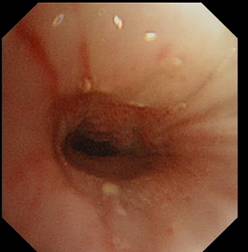

右主支气管: 荧光支气管镜(左图) 白光支气管镜 (右图)

术后病理示鳞状细胞癌,并准确判断手术切除范围。